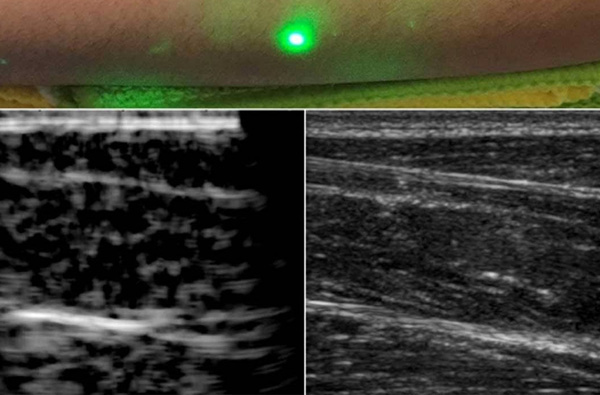

全球首張人類(lèi)激光超聲波圖像問(wèn)世

東莞盈創(chuàng)激光科技有限公司,詳細(xì)概述,與其他成像方法相比,超聲成像具有非電離、成本相對(duì)較低、便于攜帶等優(yōu)點(diǎn)。 如果需要進(jìn)行超聲波檢查,但患者不能忍受探針接觸皮膚,例如嬰兒或燒傷患者,則需要更好的技術(shù)。 現(xiàn)在,麻省...